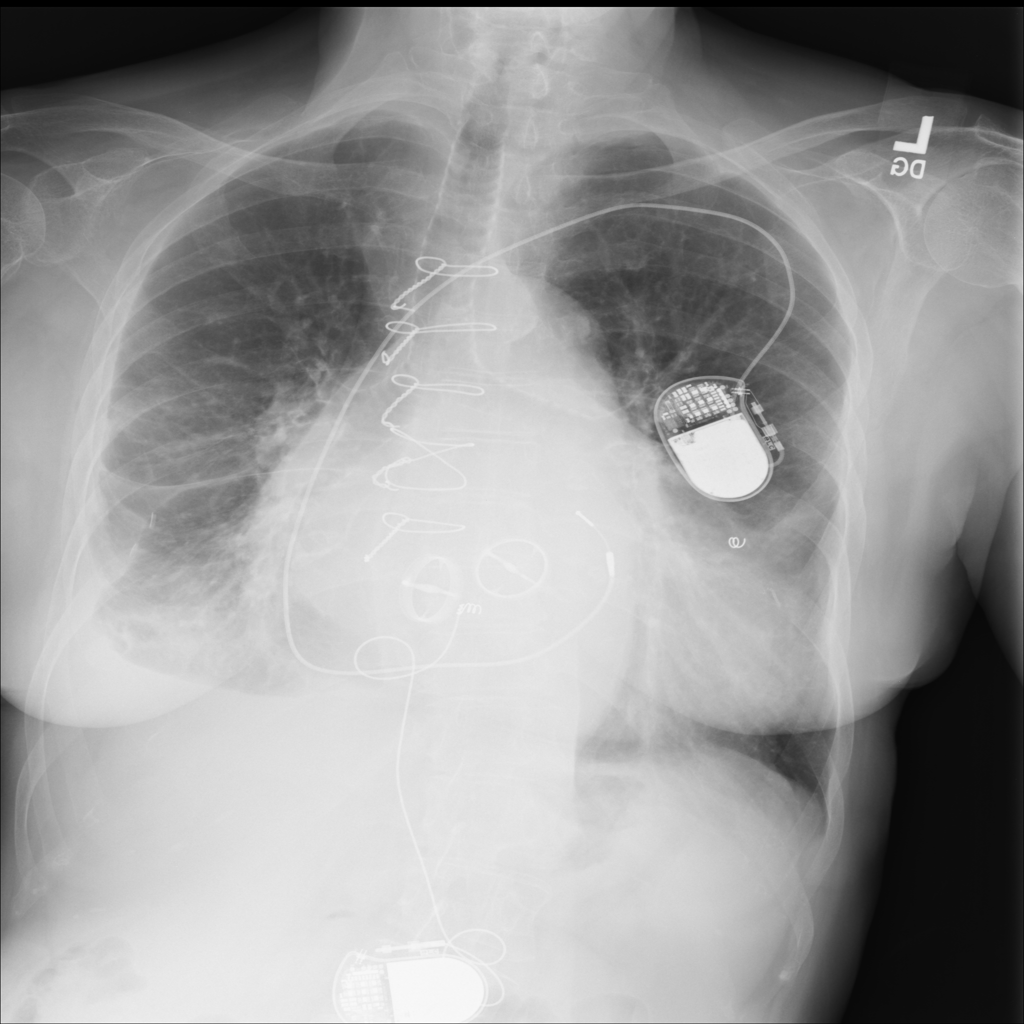

PAT-3384 · IMG-000Cardiomegaly

PAT-3384 · IMG-000

AP